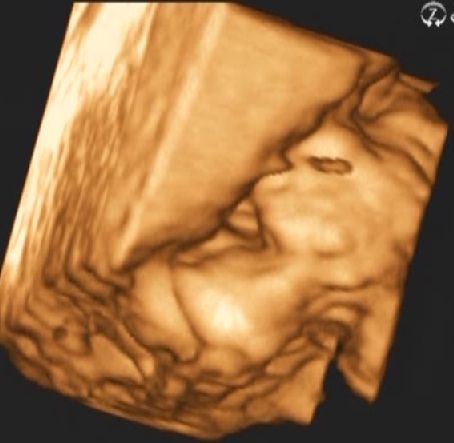

Hoztam én is képeket :P Profilból, ásítós, tappancsos na meg a bizonyíték, hogy kisfiú :wink:

óóóóó kérem micsoda képet :D:D:D Imádnivaló pasi már most, ez látszik :wink:

Nagyon édes, azok a tappancsok :D:D:D és a bizonyíték is jóóóóó :wink:

Barbuss: az a tappancsos kep halali, na es a futtyentos, a kicsi zacsi nagyon jol latszik...